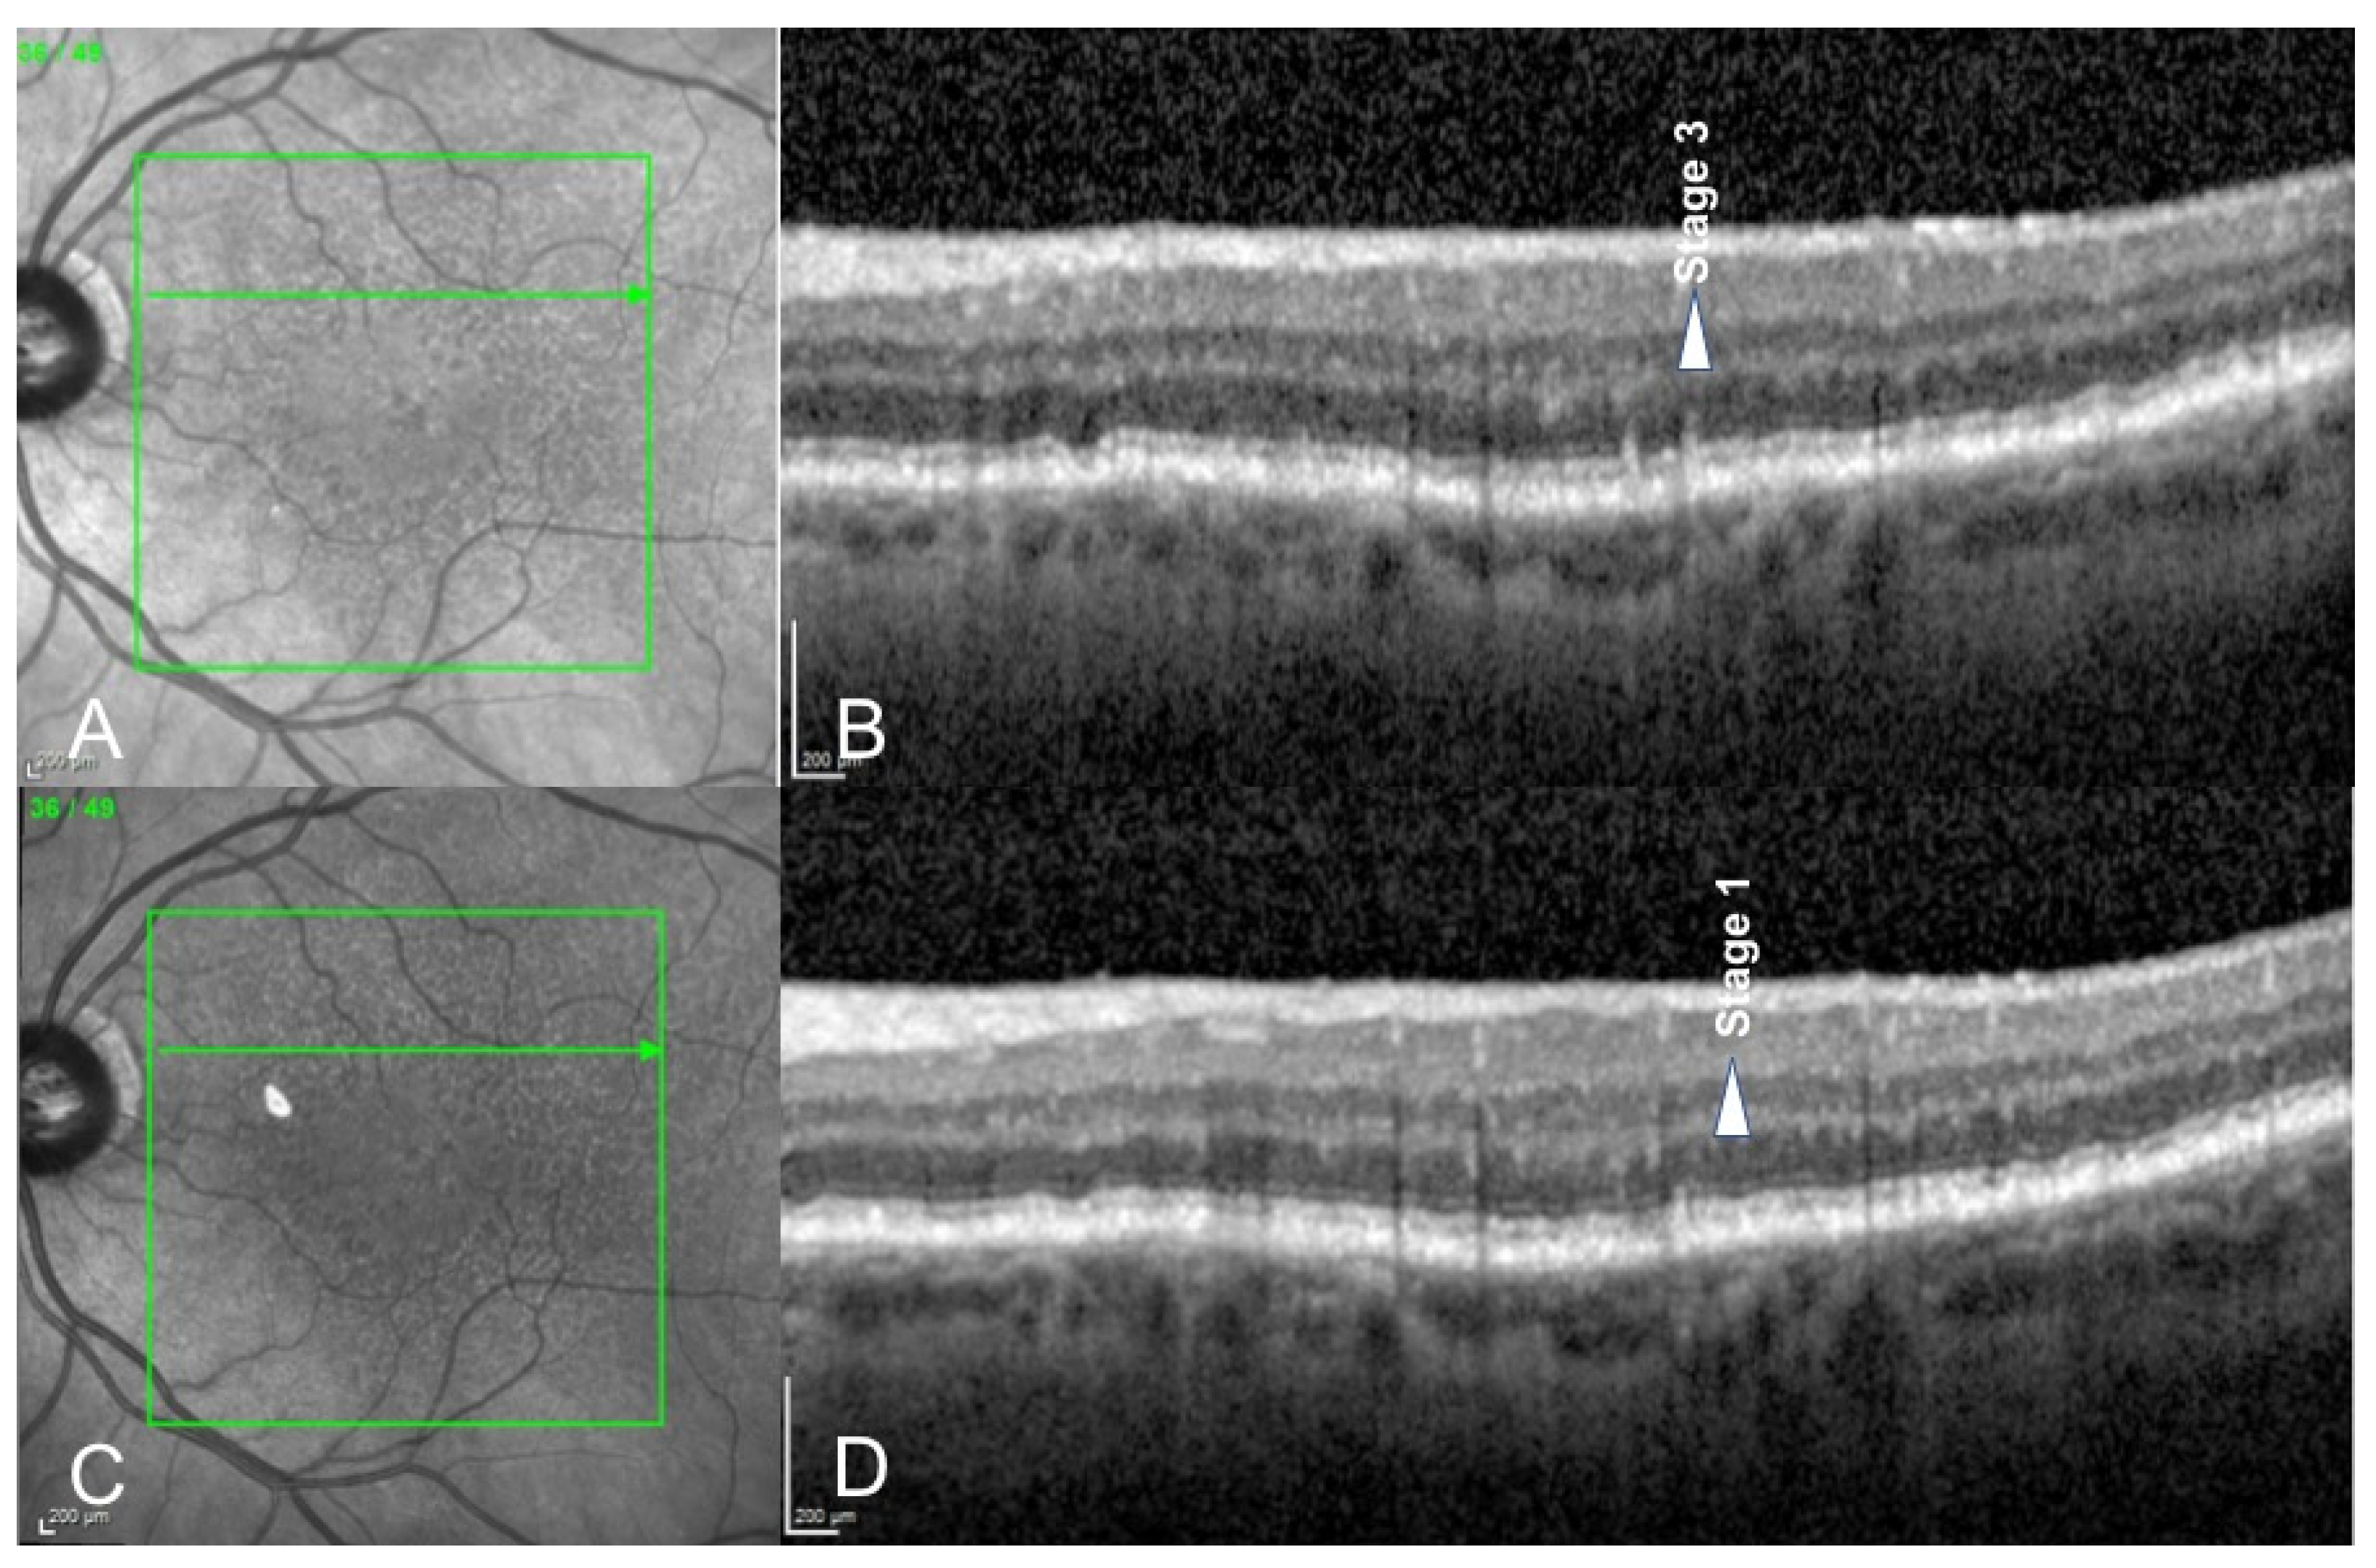

- Querques, G.; Canoui-Poitrine, F.; Coscas, F.; Massamba, N.; Querques, L.; Mimoun, G.; Bandello, F.; Souied, E.H. Analysis of Progression of Reticular Pseudodrusen by Spectral Domain–Optical Coherence Tomography. Investig. Ophthalmol. Vis. Sci. 2012, 53, 1264–1270. [Google Scholar] [CrossRef] [PubMed]